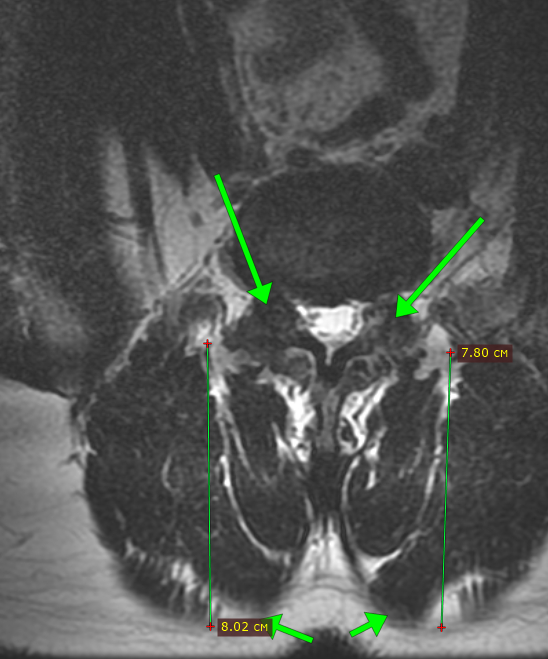

Стрелками обозначены грыжи дисков.

тем кто в теме уже становится понятно - вряд ли дело в них.

Стрелками показаны суставы позвоночника, которые жутко деформированы, как будто там артроз сотой степени бабушки 90 лет. Но перед нами молодой человек.

к тому же имеется 8-мисантиметровая мышечная ткань, что безусловно хорошо, но это ОЧЕНЬ много. Так не бывает просто так, даже у элитных спортсменов редко видишь такое, а перед нами обыватель.